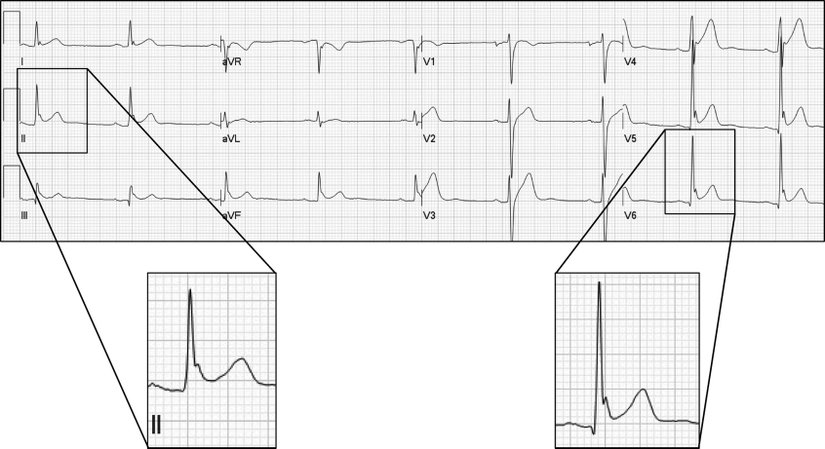

Kalpteki ileti sistemi bozuklukları, örneğin kalıtsal Wolff Parkinson White sendromu (PRKAG2 gen mutasyonu), konjenital uzun QT sendromu (KCNQ1, KCNQ2 ve SCN5A gen mutasyonları), Brugada sendromu (SCN5A gen mutasyonu) AKÖ ile yakından ilişkilidir. Kalpte iletim sistemindeki bozukluklar sonucu ventriküler taşikardi ya da hızlı ve düzensiz şekilde uyarılan ventriküllerin senkronize kasılma fonksiyonunu kaybederek "kalp titremesi" şeklinde tasvir edebileceğimiz ventriküler fibrilasyon gelişebilir ki bu da defibrilasyon yapılmazsa ölüme neden olabilir. Atletler ve sporcularda gördüğümüz aniden ölümlerin artmış efor durumlarından meydana gelen ritmik bozukluklar ile ilişkisi vardır.

Çoğu vaka geliştiği andan itibaren 1 saat içinde, hatta bazen isminin hakkını fazlasıyla verecek şekilde çok hızlı ölüme neden olur. Yeterli zaman diliminde tanı için hastalık öyküsü, anamnez, EKG, Holter monitörü ile değişiklikleri takip etmek hatta koroner anjiyografi uygulanması gerekebilir.